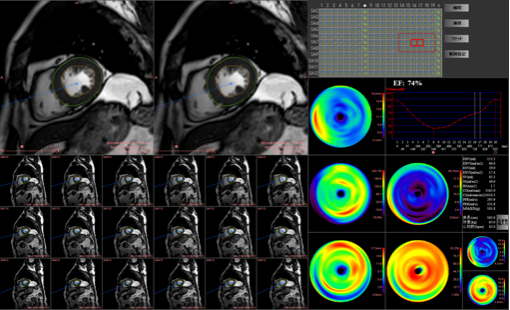

左心室機能解析:心臓の機能解析が可能です。

非造影心臓MRI

T1 mapping:左心室の性状評価が可能です。